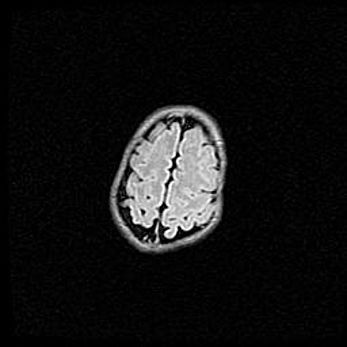

Неполная лизэнцефалия (пахигирия). Открытая гидроцефалия.

Возраст: 17 дней

Вес: 3110 г

Пол: мужской

Окружность головы: 33,5 см

Срок гестации: 35-36 недель

Лизэнцефалия—недоразвитие корковой пластинки и мозговых извилин в результате нарушения миграции нейронов коры. Поверхность мозговых полушарий гладкая. Микроскопически выявляется отсутствие нормальных слоев коры и скопление групп нейронов в подкорковом белом веществе.

Пахигирия—уменьшение числа вторичных извилин. В пораженном полушарии нервные клетки образуют толстый недифференцированный слой с неправильно расположенными нервными волокнами и группами гетеротопных клеток. Нервные клетки незрелые. Белое вещество истончено. При этом нередко аномально развит корково-спинномозговой путь.